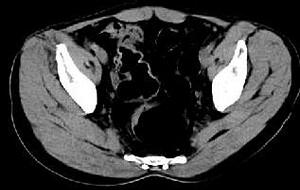

问题 女,51岁,腹胀、腹痛、进行性消瘦,影像检查如下图,最佳诊断是 ( )

选项 A、乙状结肠淋巴瘤 B、乙状结肠息肉 C、乙状结肠结核 D、乙状结肠癌 E、乙状结肠crohn病

答案 D